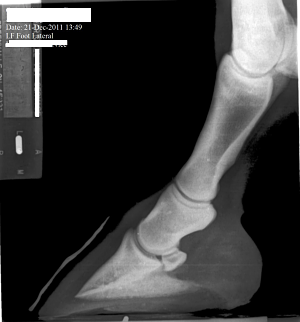

Posted on Sunday, Jan 29, 2012 - 7:53 pm: Thanks Cheryl. It was late Friday when I posted, and I figured everyone would be off having a week end. Anyway, for what it's worth, I see the beginning possibly of side bone on the lateral side. I see the pastern joint angle does not match the angles of the fetlock and coffin joint. I cannot tell where the coffin joint is in relation to the coronary band. She has long under run heels and long toes. I don't know if the depth/shape of the collateral grooves tells me anything. The ski tip on the front of the coffin bone bothers me especially on a horse only 3. And is there a small bit or rotation down as well? I don't understand in the X-Ray why her sole appears to be bearing the weight and the hoof walls are off the ground. Is this really how she was prior to 'corrective' shoeing or is this X-Ray poorly taken or am I just poor at interpreting it. Or has her hoof mechanism sunk into the hoof capsule some? I do not have vet remarks for these X-Rays. |

Posted on Sunday, Jan 29, 2012 - 8:16 pm: left front The first X-Ray cut off the fetlock joint. This was not an editing error.The coffin joint looks uneven to me. Bigger space on the medial side. What does that mean? Nothing or something. I can't tell if this mare is built like a stack of playing cards or not(remember stacking cards like the wobbly Leaning tower of Pisa?). And how come the left lateral view the hoof wall is on the block but the right lateral view the hoof wall is off the block...is this an operator error or wonky foot? |

Posted on Monday, Jan 30, 2012 - 12:03 pm: Ann, look at the left lateral radiograph. The small hook at the top, lateral side of the coffin bone. It sticks up a wee bit higher than the other side and is perhaps? moving a bit past the beginning of the coffin joint. As I understand it sidebone isn't always related to a lameness issue, and many older horses have it. However, this is a 3 yr old. I "think" it is a minor issue... |

Posted on Tuesday, Jan 31, 2012 - 8:12 am: Hello Vicki,In general I avoid interpreting radiographs on the internet as the quality of the images here are not high enough to do a good job and the amount of time required to look at all aspects of the radiograph. I do invite members to put up radiographs and I will comment on any diagnosis made by the veterinarian who took the radiographs. That said I do think the RF foot in the front appears to have an overly long toe and corresponding toe flare and underrun heel. I don't see these issues in the L fore. The problem with assessing the conformational issues your bring forth is that technique and how the radiographs are taken can greatly effect the relationship between the bones and create false impressions. For instance all a horse has to do is stand a little forward over the foot and the normal pastern will not be aligned. The conformation issues you raise are best assessed looking that the horse while standing square and moving in a straight line than by a static set of radiographs. DrO |